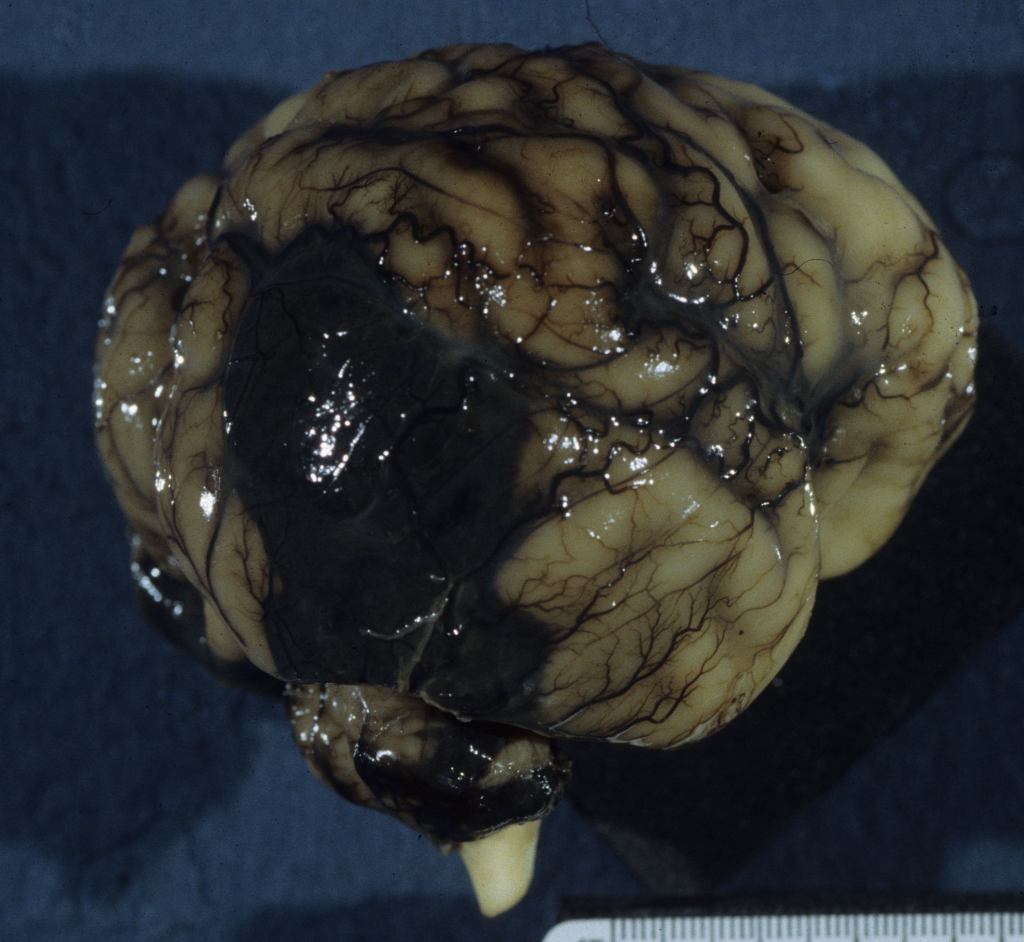

Intraventricular hemorrhage (IVH):

Intraventricular hemorrhage is usually the result of germinal matrix hemorrhage or hemorrhage from periventricular leukomalacia. The germinal matrix exists from early gestation to term as a reserve of immature cells that will become neurons and glia. The amount decreases after 33 weeks of gestation. The risk of IVH synchronously decreases with the maturation of the germinal matrix. Hemorrhage in this soft embryonic appearing tissue with prominent thin-walled vessels may occur in response to various risks including hypoxia, cytokines, or suddenly changing vascular pressures. Most hemorrhages are identified after birth. However, intraventricular hemorrhage can be found in previable fetuses at autopsy (Fig 1).

Grossly, in the intact brain, blood in the ventricles often seeps and pools around the base of the brain (Fig 2).

A simple grading system for IVH is: Grade 1: hemorrhage confined to the germinal matrix; Grade 2 hemorrhage into but not expanding the ventricle; Grade3 hemorrhage expanding the ventricle; Grade 4 hemorrhage into the white matter. Since the blood is likely to follow the path of least resistance, these Grade 4 hemorrhages likely flow into areas of periventricular leukomalacia which are also more frequent in more premature infants (Fig 3).